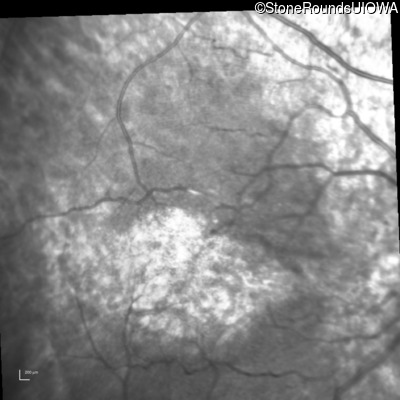

Infrared Fundus Photograph - Right - 20/160

Exemplar

Infrared Fundus Photograph - Left - 20/80 -1